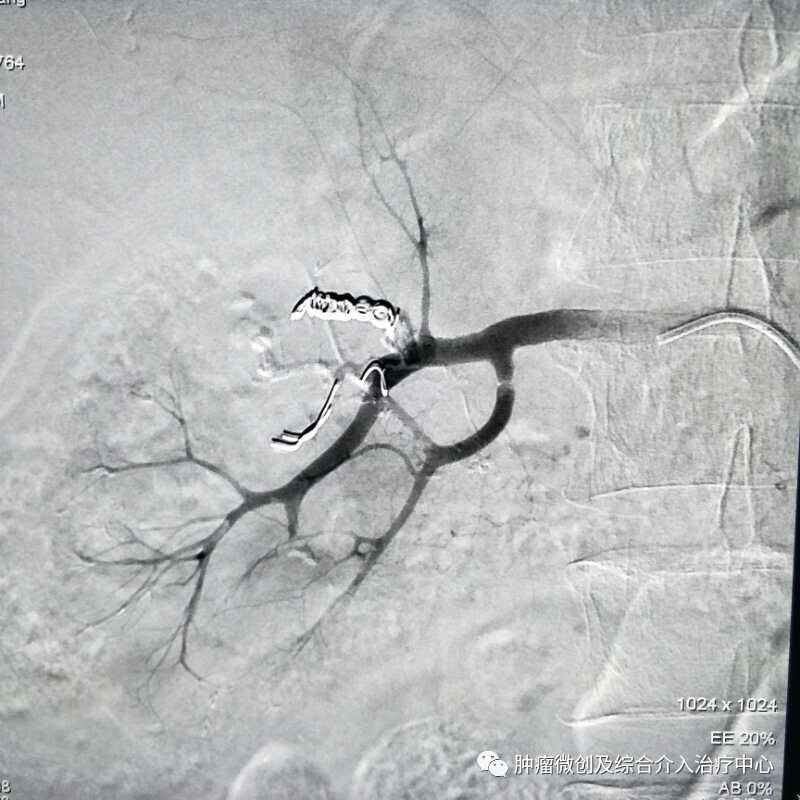

(经皮穿肝-门静脉穿刺成功,门脉高压,门静脉扩张明显)

(食管胃底静脉栓塞术,在血管根部将破裂的上消化道出血血管栓塞完全,即可止血)项目简介:肝硬化门脉高压失代偿期临床表现为反复消化道出血等,患者一般情况欠佳,传统治疗难以改善。食管胃底静脉+胃冠状静脉栓塞术暨经皮肤穿门脉食管胃底+胃冠状静脉栓塞明显降低因消化道大出血导致休克及死亡的风险; 结合内科治疗,其顽固性腹水症状可迅速消退,改善患者生活质量。10肝硬化门脉高压失代偿介入治疗(TIPS术)